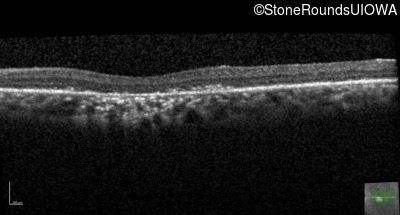

The clinical features supporting the diagnosis of Bardet Biedl syndrome in this patient include: bone-spicule-like pigmentation, narrowed arterioles and macular atrophy on ophthalmoscopy; photoreceptor loss on OCT; ulnar polydactyly, obesity, abnormal cognition, hypertension; and, normally sighted parents.